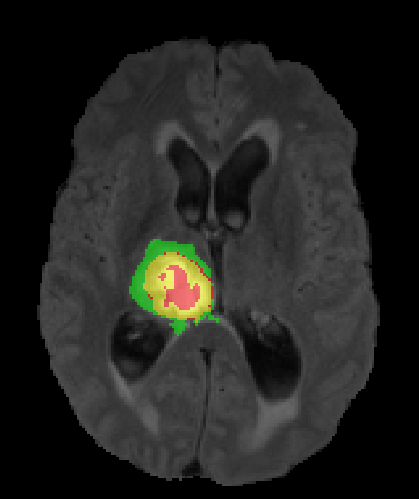

We argue that the sub-optimal paradigm of processing different abstractions within a single CNN pipeline can be remedied through the effective processing of information in a structured manner. Consequently, we devise strategies for disentangling the edge and texture information within a single training pipeline. Figure 2 illustrates how our proposed module, dubbed EG-CNN, can be paired with any existing CNN encoder-decoder to improve segmentation quality near intensity edges. We have applied our EG-CNN to the tasks of brain and liver tumor segmentation in medical images (Figure 3).

(1) Brain MR (2) Liver MR (3) Liver CT (4) Lung CT